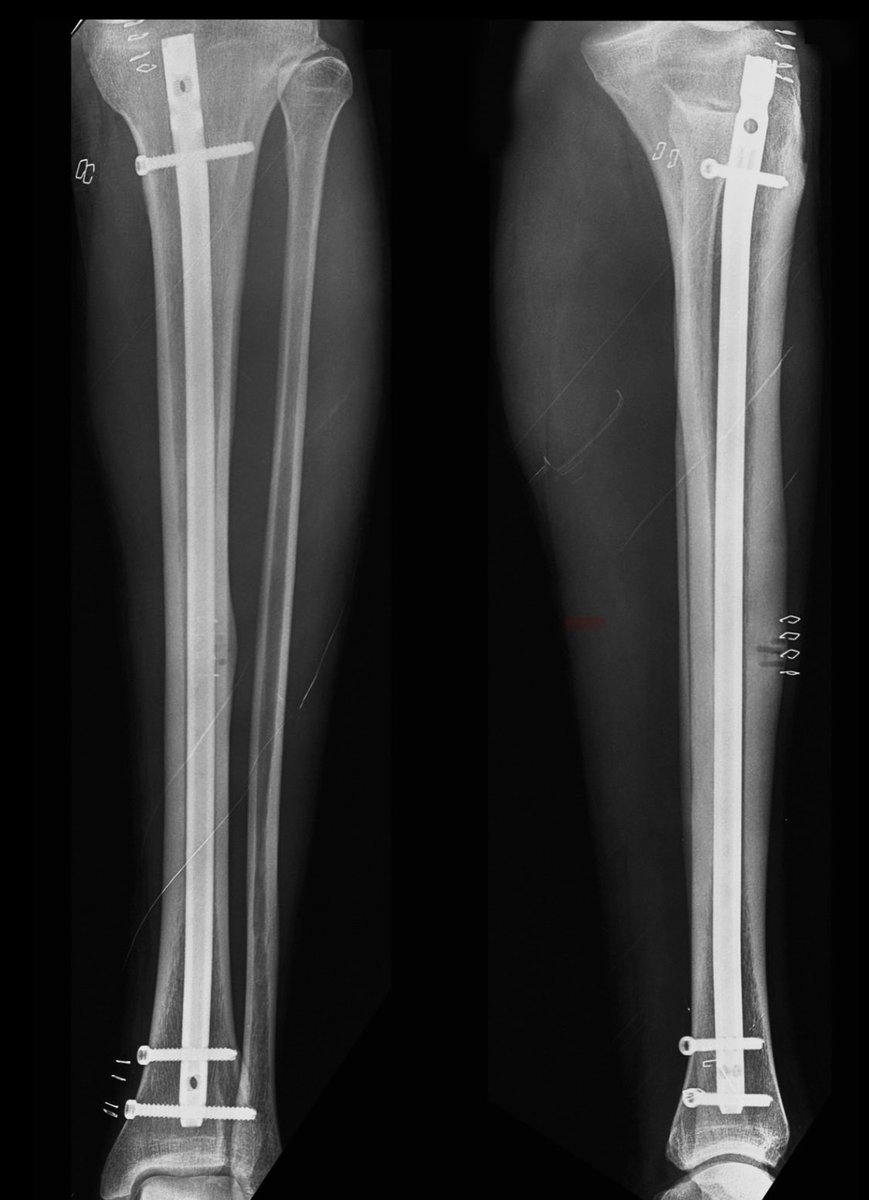

-ايضاً من العوامل طريقة علاج الكسر

هل كان جراحياً او تحفظي

حيث المبدأ الاساسي في الجراحة اعادة الطرف المكسور الى اقصى وضعية مناسبة لتساعد المريض على العودة الى الحركة واستعادة حياته الطبيعيه باسرع وقت

ومن اهم العوامل المحددة للتاهيل هي نوعية العملية الجراحية وطريقة تثبيت الكسر

فيكون القرار خلال العملية الجراحية، فالجراح على دراية كامله عن وضعية الكسر وإمكانية استعادة المشي بشكل مباشر

فنوع التثبيت المستخدم يلعب دور جوهري عن نوع التأهيل